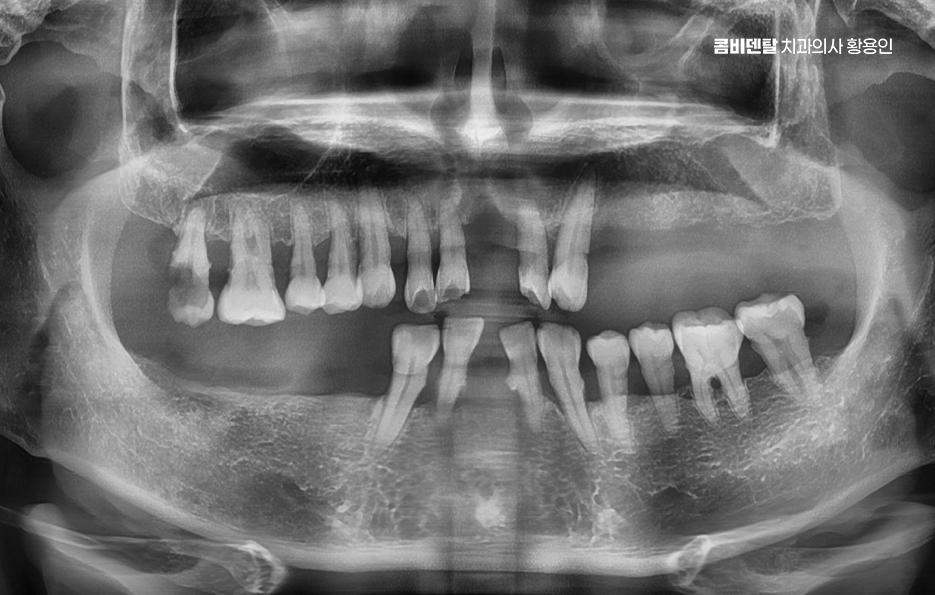

그렇다면 뼈이식을 언제, 어떻게 계획해야 하는지가 중요한데 첫 번째는 임플란트 식립 전 단계에서 충분한 영상 진단과 분석을 통해 뼈의 양과 질을 정밀하게 평가해야 하며 단순 파노라마 X-ray만으로는 확인이 어려운 입체적인 골량이나 신경과의 거리, 부비동 위치 등을 정확히 파악하려면 3D CT 촬영이 필수적이고 이를 통해 상악동 거상술이 필요한지 등을 판단할 수 있어요.